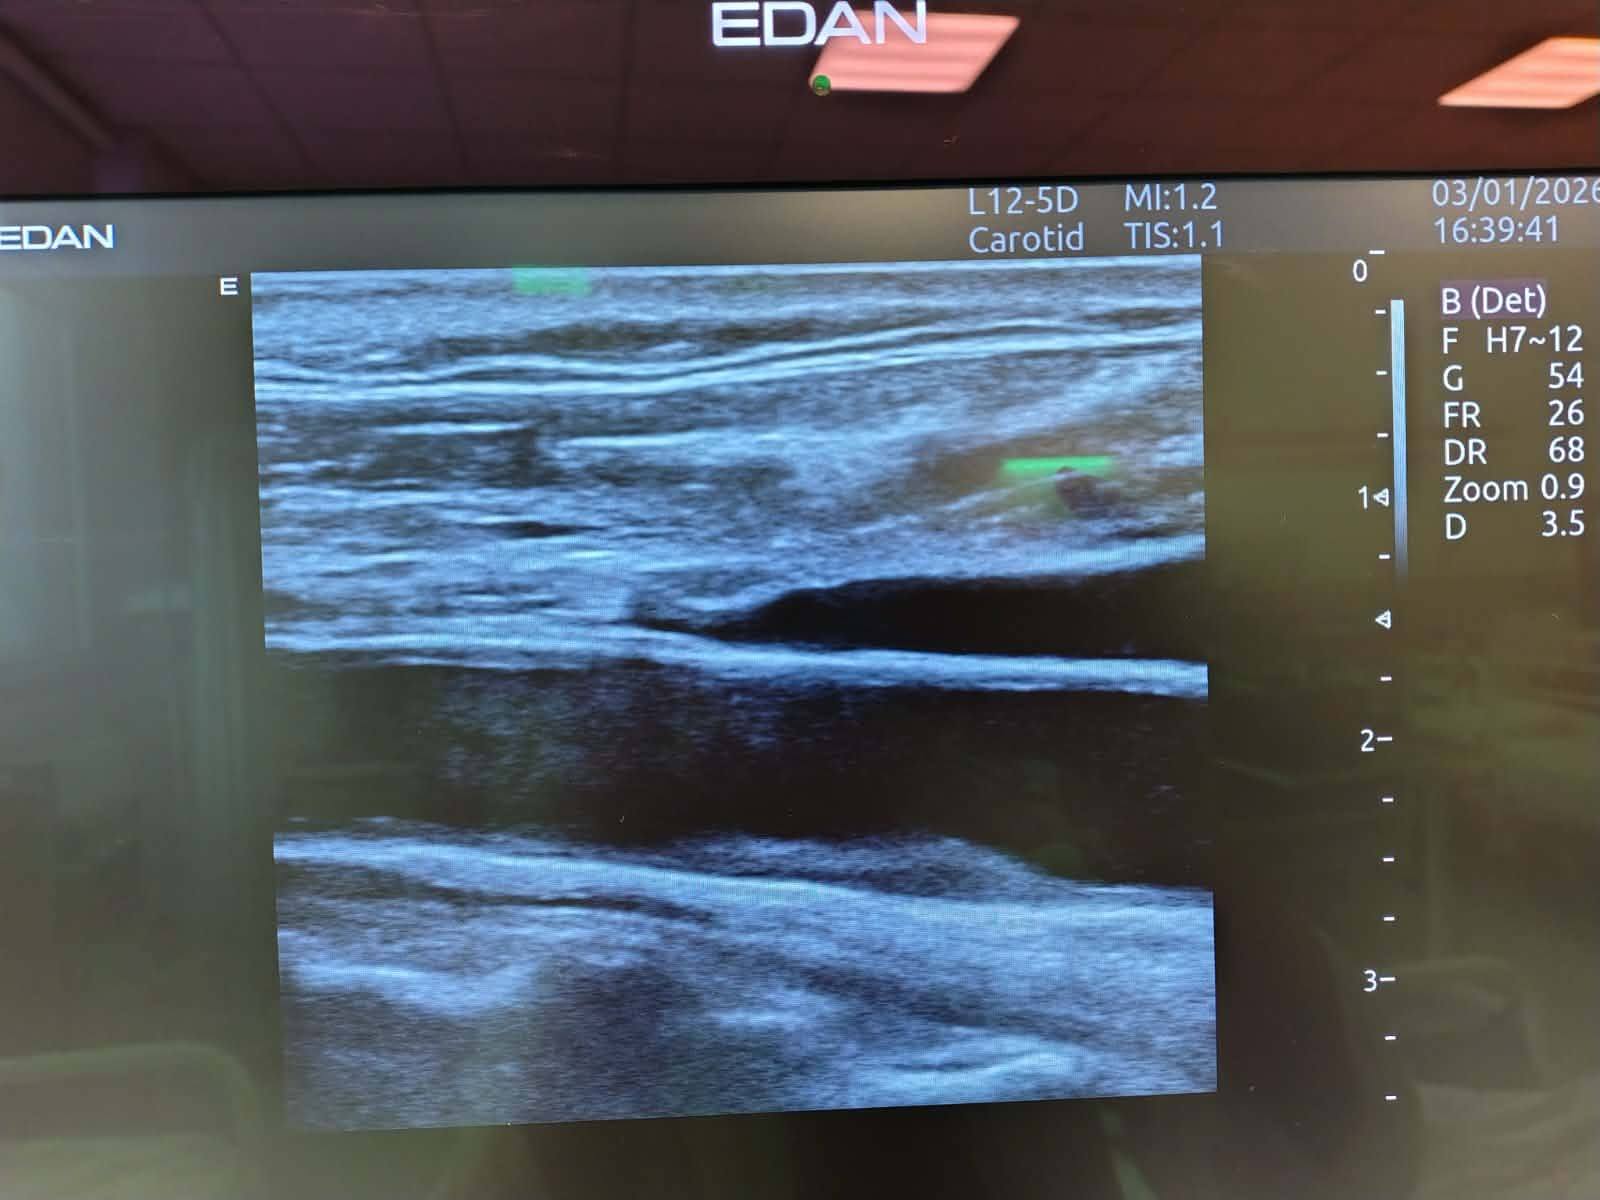

Првиот пациент, млад маж на 29-годишна возраст, беше примен поради нагло настаната слабост на левата рака, асиметрија на лицето и отежнат, неразбирлив говор.

Благодарение на брзата дијагностика и навремената примена на терапијата, по интервенцијата пациентот е во целост без невролошки последици и без појава на компликации.